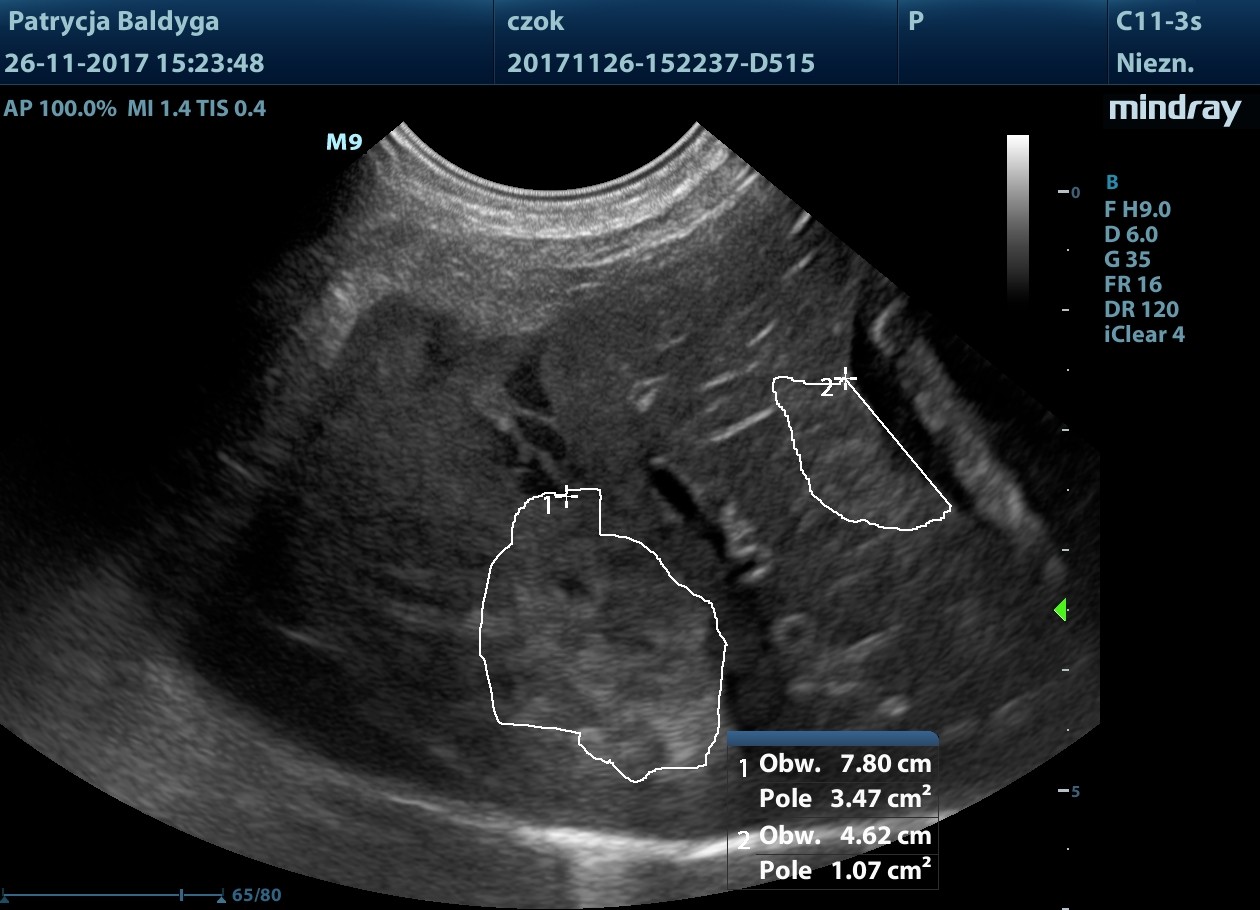

Miąższ szczególnie płatów lewych o miejscowo wzmożonej echogeniczności, nieco nieregularnej torebce, z obecnością zmiany ogniskowej najpewniej krwiaka pourazowego ok. 3,2 x 1,6 cm w płacie lewym bocznym modulującego znacznie torebkę powierzchni trzewnej.

Obecność znacznie zwiększonych ilości wolnego, nieco zagęszczonego płynu w jamie otrzewnej, widocznego w dużej ilości przypęcherzowo, przywątrobowo, pomiędzy pętlami jelit oraz śladowo również w przestrzeni zaotrzewnowej

- co nasuwa duże podejrzenie krwotoku masywnego, najpewniej z wątroby, wskazanie do laparotomii zwiadowczej.